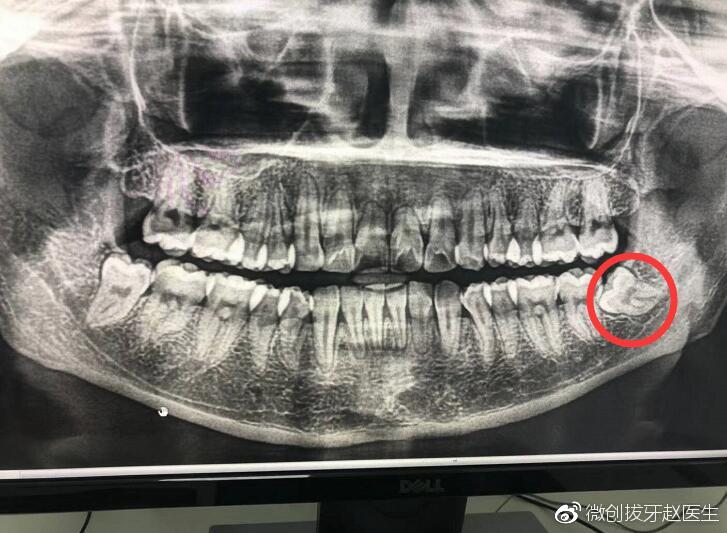

微创拔牙赵医生讲述:拔智齿后谨记4个注意事项

727x533 - 66KB - JPEG